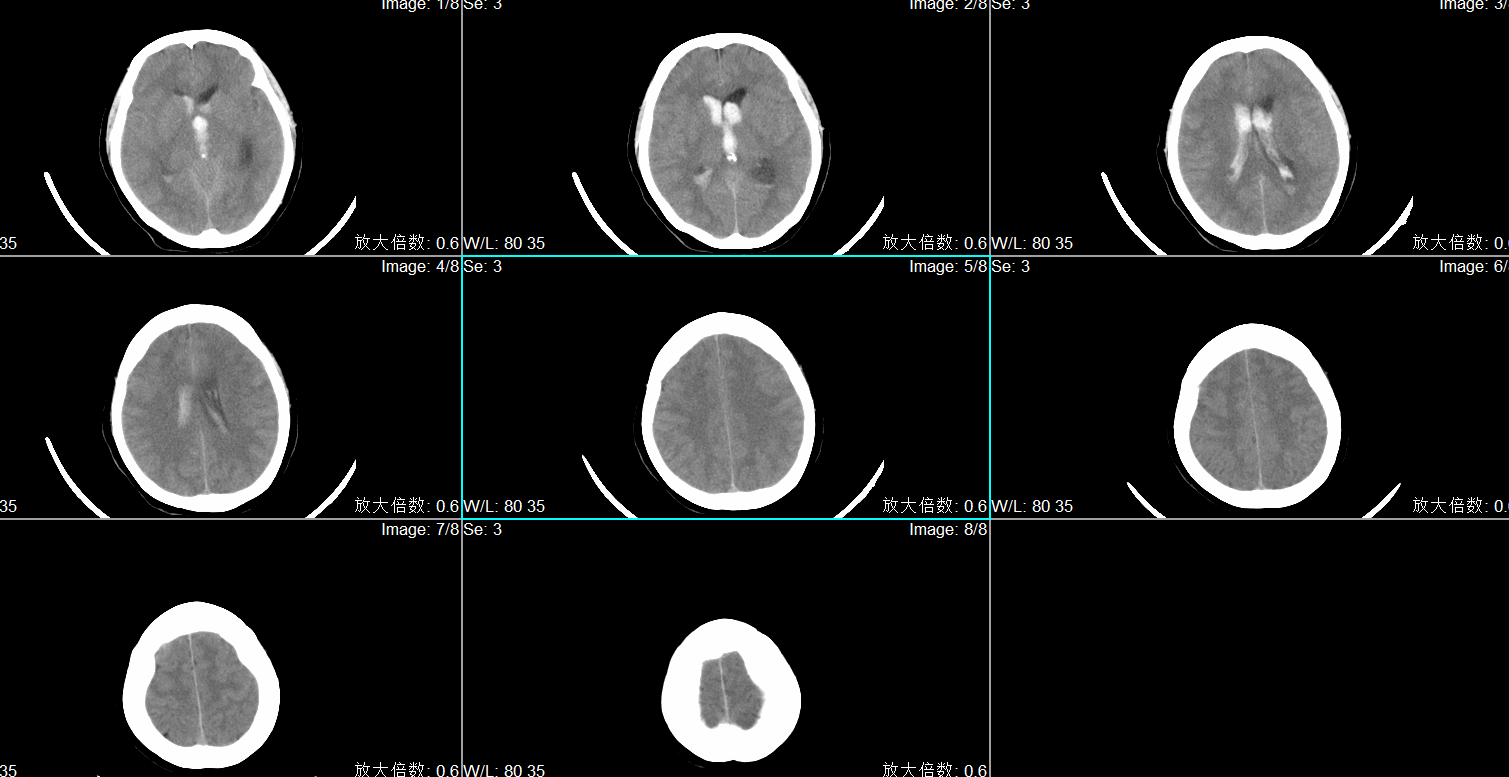

入院头CT显示小脑蚓部出血破入第四脑室、第三脑室及第四脑室。

入院诊断为:1.小脑蚓部出血 2.高血压病3级(极高危)3.吸入性肺炎。

术前头CT